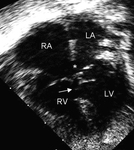

Imagen de ecocardiografía de 4 cámaras apical de una comunicación interauricular (CIA) de tipo ostium primum (flecha). (AD) aurícula derecha; (AI) aurícula izquierda; (VI) ventrículo izquierdo

Imagen cortesía de Patrick W. O'Leary, MD